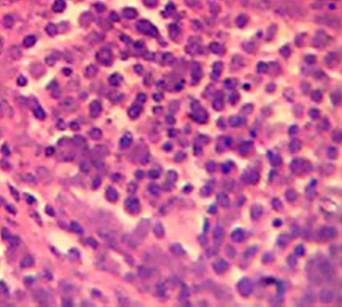

Effect of MSEAO on vital organs. Gross and histopathological examinations showed no significant (P > 0.05) lesions in the vital tissues (Bursa of Fabricius and spleen) examined as compared to the control group. See Figures 1 and 2.

Figure 1 Bursa of Fabricius showing no obvious lesions 48 h post-administration. H&E X 400.